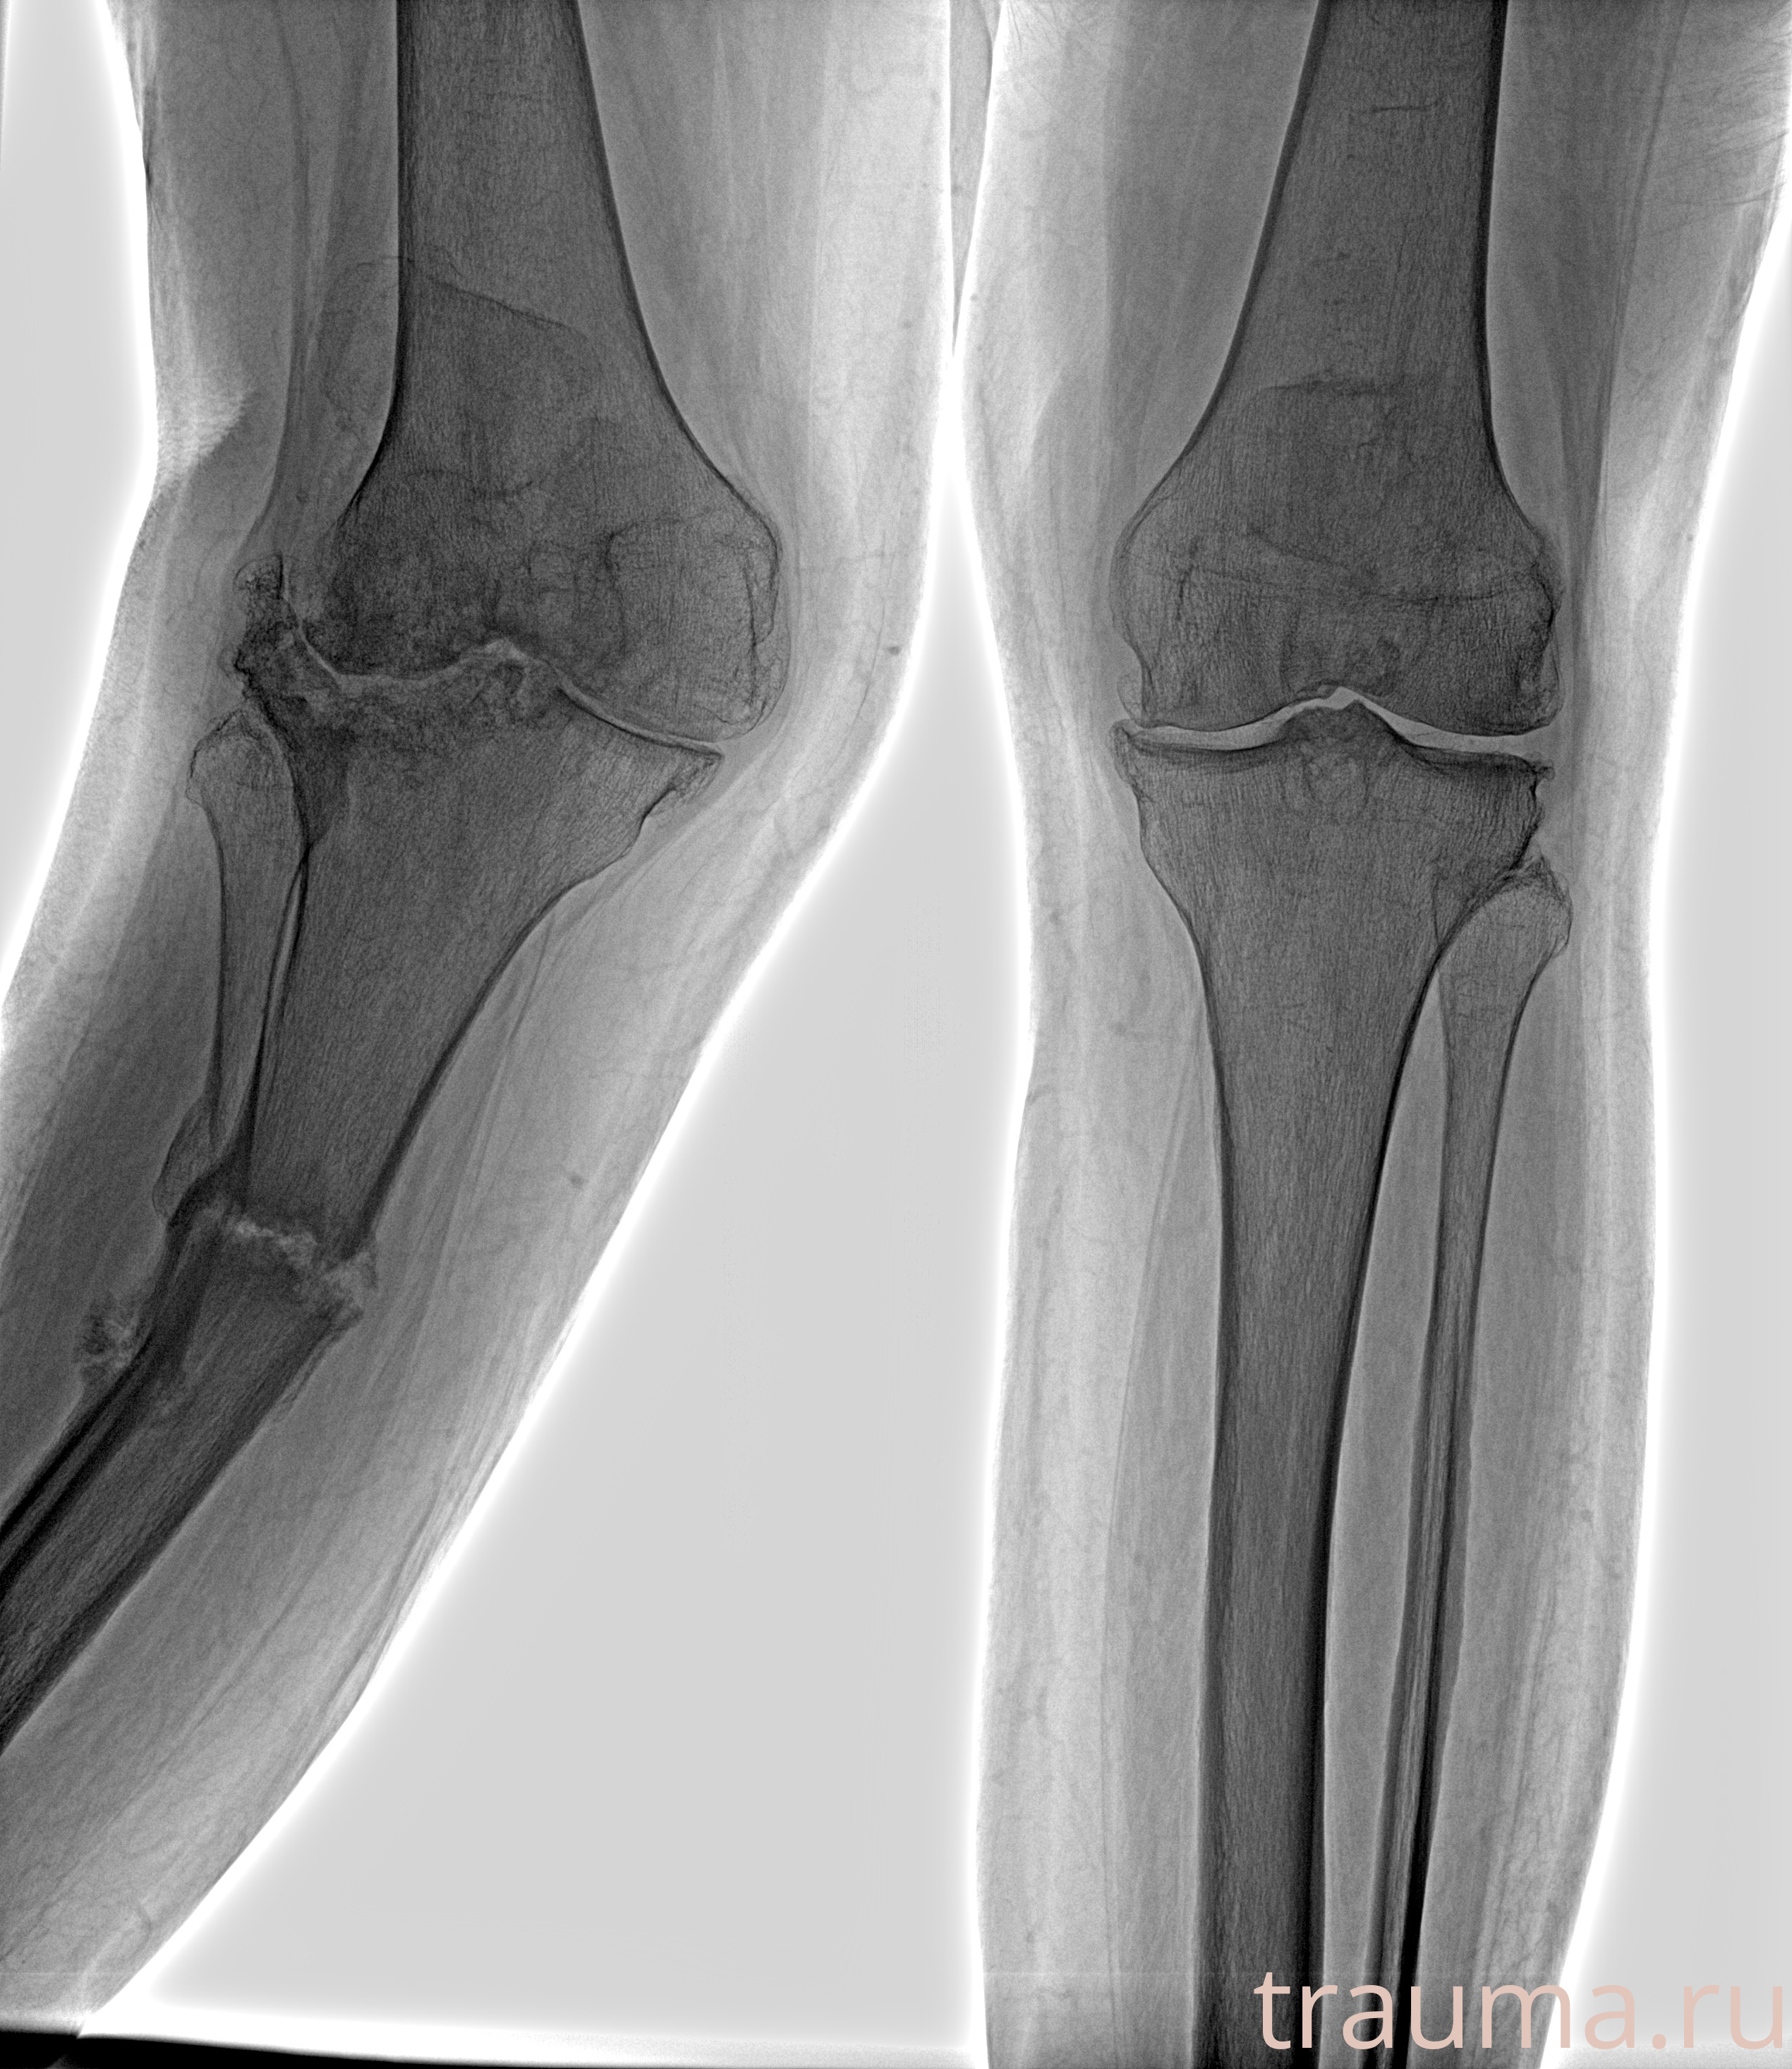

Рентгенограммы

Рентген на дому: по вашему адресу приезжает врач-рентгенолог, травматолог-ортопед с мобильным рентгеновским аппаратом, проводит диагностику травмы или заболевания, делает необходимые рентгенограммы, дает рекомендации по дальнейшему лечению. Получить качественные снимки в домашних условиях возможно благодаря уникальной методике, разработанной МосРентген Центром для института  Склифосовского